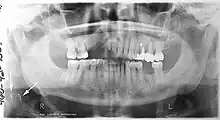

Epidemiology: general public and high risk groups

Additional research projects have further determined the prevalence rate of these atheromas in the general population (3–5%)[8][9] and among high-risk groups (over 25% in: recent stroke victims,[10] individuals with obstructive sleep apnea syndrome,[11][12][13] postmenopausal women,[14] type 2 diabetics,[15][13][16] individuals with dilated cardiomyopathy,[17][13] and among individuals who have received radiotherapy directed at the neck,[18][19]). These findings have been corroborated by other several other researchers.[20][21][22][23][13]

Dental infection and atherosclerosis

Atherosclerosis is attributed to risk factors that include cigarette smoking, hyperlipidemia, obesity, diabetes mellitus, and hypertension (high blood pressure). These factors, however, do not fully account for the risk of disease. Atherosclerosis has been conceptualized as a chronic inflammatory response to endothelial cell injury[24] and dysfunction possibly arising from chronic dental infection. In 2010, using the previously validated Mattila panoramic radiographic index to quantify the totality of dental infection (i.e., periapical and furcal lesions, pericoronitis sites, carious tooth roots, teeth with pulpal caries, and vertical bony defects), Friedlander’s group determined that individuals with carotid artery atheromas on their panoramic radiographs had significantly greater amounts of dental infection/inflammation than atherogenic risk-matched controls devoid of radiographic atheromas.[25][26] While the Mattila index had been previously used to relate the extent of dental infection to coronary artery disease, this research is the first to link the full range of dental disease that it measures to panoramic radiographs evidencing calcified carotid artery atherosclerosis.